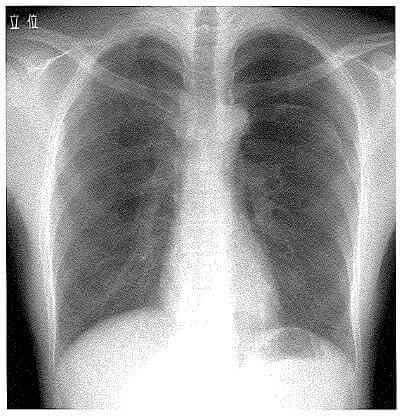

問題54.58歳の男性。肩こりが強いため鍼治療を受けていた。いつものように鍼治療を受けて帰宅したが、左胸部痛が出現したため救急外来を受診した。発熱はない。単純エックス線写真を下に示す。

この病態で正しいのはどれか。

・単純エックス線写真:左上胸の肺野が全体的に黒く(透過性亢進)、血管影が消失。

4.〇 正しい。気胸が最も疑われる。なぜなら、鍼治療後に片側胸痛が出現し、画像で該当側の肺の虚脱と胸腔内の透過性亢進を認めるため。鍼による肺穿刺が原因で医原性気胸を発症していると考えられる。